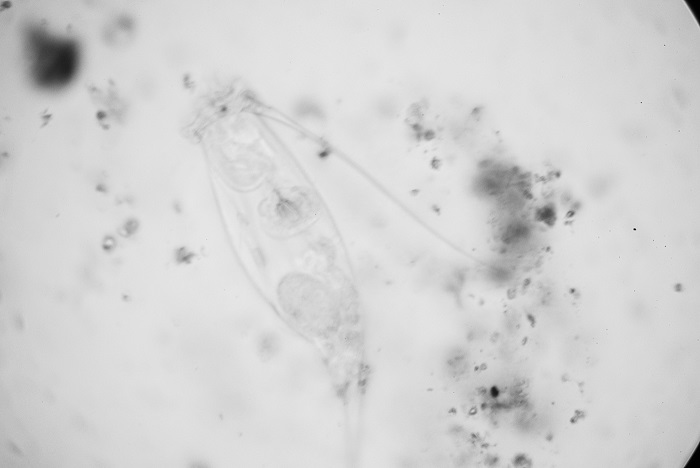

Then things got worse. It all started when I was prescribed Wellbutrin, and then Effexor. I was in the lab, quietly minding my own business, fixing a water bath. Suddenly, I heard a loud,”MmmmmMMMMMHHHH!!!” in my ear. The sound was positively human. Startled, I flinched and asked my coworker, “Did you hear that?” Of course, he hadn’t.